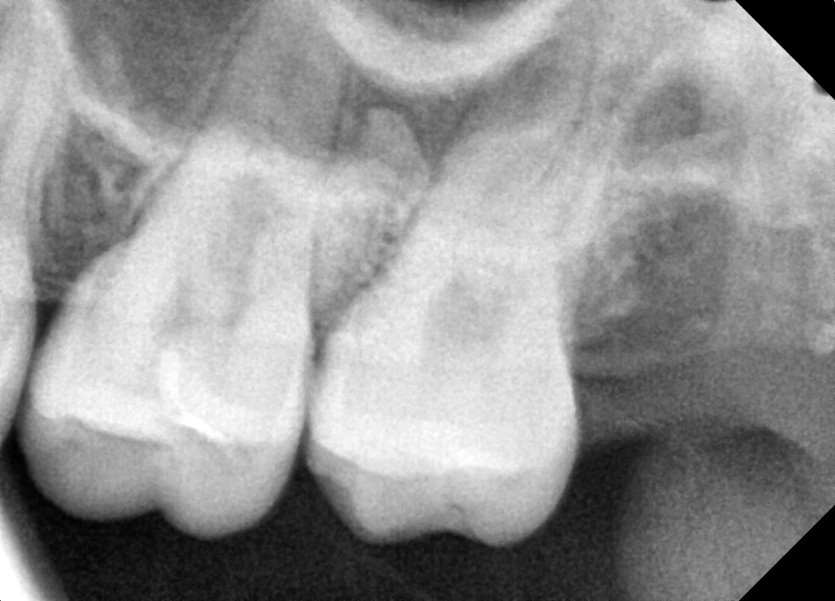

#28,38 사랑니 발치

구강 외과 전문의가 당일 발치했습니다.